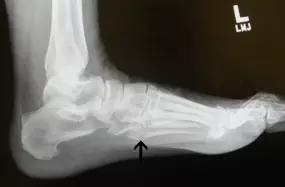

14.第五跖骨骨折

第五跖骨基底部骨折的不同类型:Stress 骨折;Jones 骨折:第五跖骨基底部以远 1 英寸内的骨折称为 Jones 骨折; Avulsion 骨折。

(来源:Radiopaedia)

Stress 骨折(来源:OrthoInfo-AAOS)

Jones 骨折正位片(来源:Radiopaedia)

Jones 骨折斜位片(来源:Radiopaedia)

第五跖骨骨折还有 dancer’s fracture。